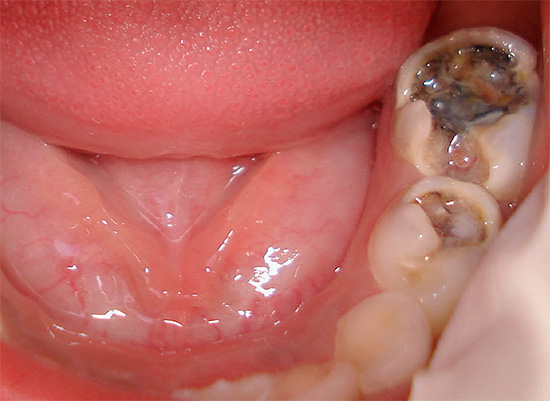

Foto di un dente con una profonda cavità cariata, che ha portato allo sviluppo della pulpite:

Foto di carie profonde sul dente anteriore: